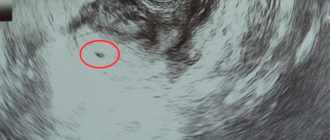

Показывает ли беременность на ранних сроках до задержки на УЗИ: диагностика, расшифровка, определение на